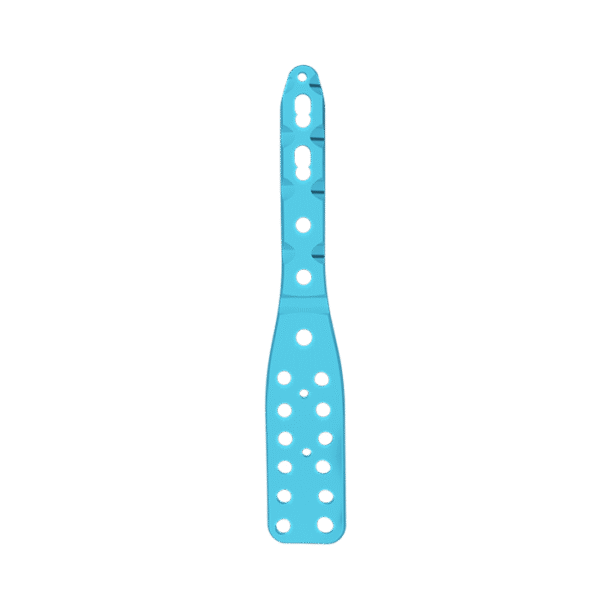

- Tres filas de orificios en el extremo distal, para fijar el calcáneo; Tornillo de fijación divergente, para mejorar la buena sujeción.

- Tres filas de agujeros en el medio, para fijar el astrágalo; tornillo de fijación divergente, para proporcionar una fijación estable

- Diseño de perfil bajo, para reducir la irritación de los tejidos blandos.

- Tornillo de bloqueo de 3,5 mm

- Tornillo de cortical de 3,5 mm